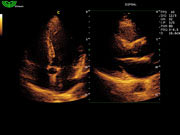

D3P64L 3.0МГц, фазированная решетка.

2.0МГц – 4.4МГц. Применения: кардиология, брюшная полость, акушерство. |